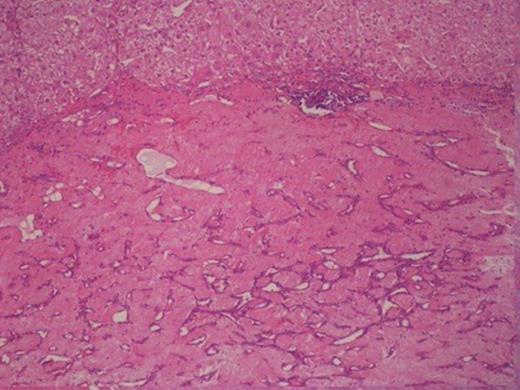

Histologically, the tumour was composed of fibroblasts that were arranged vertically. Smooth muscle cells were also recognized that apparently were remnants of the mucosal muscle layer. Also, redundant confluent lymphocytes, plasmocytes, mast cells with rare giant cell forms, as well as redundant eosinophilic granulocytes were recognized. The supernatant mucous membrane showed signs of active inflammation, and in the area of the crater, a healed ulcer was recognized. The final pathologic diagnosis was consistent with IMT that originated from the gastric wall (Figure 3).Gross examination of the nodule from the anterior wall of the fundus of the stomach showed a whitish gray elastic mass measuring 1.5x1x1cm. The tumour was identified as an incipient gastrointestinal stromal tumour that consisted of uniform neoplastic cells without nuclei atypia ((Figure 4).The node from the superior hepatic surface was identified as a syringious haemangioma. The dimensions of the haemangioma were 2x1.5x1cm and the tumour had chestnut complexion and friable texture ((Figure 5).